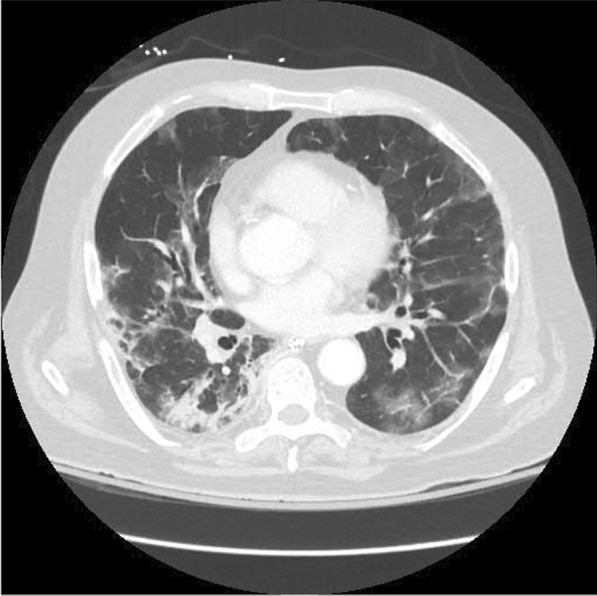

Fig. 1.

Computed tomography of the chest showing progressive COVID-19 pneumonia with bilateral ground-glass opacities and consolidation

Upon admission, the patient was alert and oriented with a blood pressure of 106/73 mmHg, pulse rate of 125 beats per minute, body temperature of 38.5 °C, and respiratory rate of 35 breaths per minute. The oxygen saturation was 89% on room air and 95% with the use of a high flow nasal cannula. A physical examination revealed diminished breath sounds in all lung fields. Laboratory tests were ordered, with the abnormal results shown in Table 1. An ultrasound of the lower extremities showed an acute left deep vein thrombosis (DVT) extending to the common femoral vein. A chest CT scan showed progressive COVID-19 pneumonia and was negative for pulmonary embolism (Fig. 1).